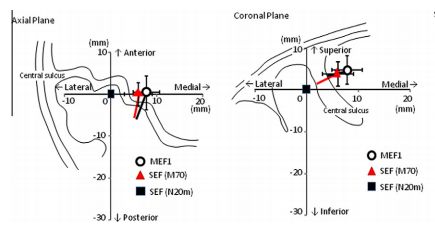

Onishi H, Sugawara K, Yamashiro K, Sato D, Suzuki M, Kirimoto H, Tamaki H, Murakami H, Kameyama S. (2013) Neuromagnetic activation following active and passive finger movements. Brain and Behavior 3:178–192.

Onishi H, Oyama M, Soma T, Sugawara K, Kirimoto H, Murakami H, Kameyama S.(2011) Muscle-afferent projection to the sensorimotor cortex after voluntary movement and motor-point stimulation: An MEG study. Clinical Neurophysiology. 122: 605-610

Sugawara K, Onishi H, Yamashiro K, Kojima S, Miyaguchi S, Kirimoto H, Tsubaki A, Tamaki H, Shirozu H, Kameyama S. The effect of anodal transcranial direct current stimulation over the primary motor or somatosensory cortices on somatosensory evoked magnetic fields.Clin Neurophysiol. 2014 (in press)

Onishi H, Sugawara K, Yamashiro K, Sato D, Suzuki M, Kirimoto H, Tamaki H, Murakami H, Kameyama S. Effect of the number of pins and inter-pin distance on somatosensory evoked magnetic fields following mechanical tactile stimulation. Brain Research, 2013, 1535:78-88